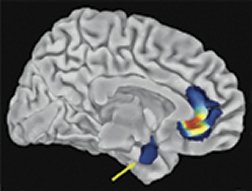

In participants with the short gene, magnetic resonance imaging revealed low numbers of neurons, and relatively sparse connections among them, in brain areas already implicated in handling negative emotions. The most prominent of these regions were the amygdala, which triggers fear responses, and the cingulate, which reins in amygdala activity.

The researchers then used functional magnetic resonance imaging to monitor blood flow in the brains of volunteers as they matched pairs of angry and fearful faces shown on a computer screen. Those volunteers with the short gene displayed little coordination between amygdala and cingulate activity, a sign of a communication breakdown. Moreover, volunteers showing the weakest connections between these brain areas reported the highest levels of daily anxiety.

In participants with the long-gene variant, amygdala activity consistently declined as cingulate activity rose. That pattern reflects the cingulate’s quelling of amygdala responses to negative facial expressions, the researchers hold.